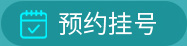

01/血尿酸的测定

血尿酸的测定以尿酸酶解法应用最广。正常情况下,男性的血尿酸为210~416μmol/L(3.5~7.0 mg/dl);女性为150~357μmol/L(2.5~6.0 mg/dl),绝经后数值接近男性。如果男性尿酸>416μmol/L(7mg/dl),女性尿酸>357μmol/L(6mg/dl)就是高尿酸血症。由于血尿酸受多种因素影响,存在波动性,应反复测定。高尿酸血症是痛风发生的最重要的生化基础,当血尿酸持续高浓度或急剧波动时,呈饱和状态的血尿酸就会结晶沉积在组织中,引起痛风的症状和体征。

03/血糖、血脂检查

在临床上,单纯只是尿酸升高的痛风患者很少,大多数的痛风患者都会伴随高血糖、高血脂、高血压,或是体重异常。而三高和高尿酸常常是相互影响,所以痛风患者需要进行血脂、血糖的检测,在调脂、降糖治疗时可以选择兼具降尿酸作用的药物以及避免会升高血尿酸的药物。